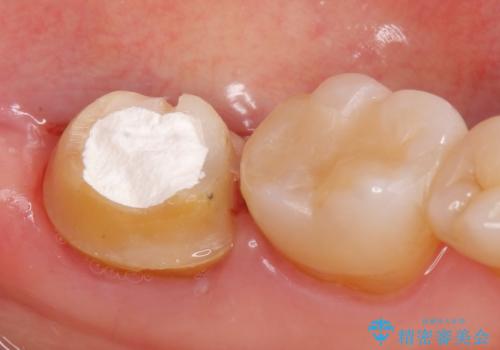

- 他院にて根管治療を行っていたが、痛みが引かないため当院での診療を希望された方の症例です。

改めて再根管治療を行い、症状の緩解を確認後、オールセラミッククラウンによる補綴を行いました。